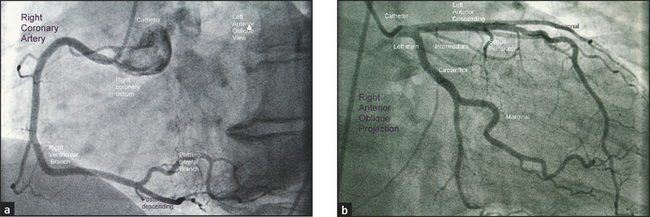

The myocardium (cardiac muscle) is supplied by the three coronaryc,1 arteries (see Figure 5.5). The left main coronary arises from the left coronary sinus of Valsalva and divides into the left anterior descending (LAD), which supplies the anterior wall of the heart, and the circumflex (Cx), which supplies the back of the heart. The right coronary artery (RCA) arises from the right sinus of Valsalva and supplies the inferior wall of the left ventricle and the right ventricle. The coronaries are often described as the epicardial coronary arteries. They must run over the surface of the heart or they would be squashed during ventricular systole.

Figure 5.5 The three coronary arteries (a) An angiogram of the right coronary artery; (b) An angiogram of the left and circumflex coronary arteries